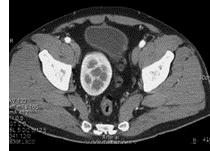

男,27岁,请根据所示图像,选择最可能诊断 ( )A、肾下垂B、游走肾C、腰段肾D、胸内肾E、盆腔肾

问题 男,27岁,请根据所示图像,选择最可能诊断 ( )

选项 A、肾下垂 B、游走肾 C、腰段肾 D、胸内肾 E、盆腔肾

答案 E